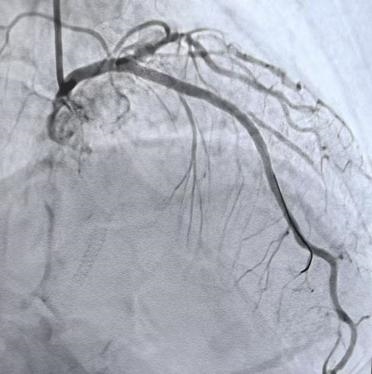

依托这一精准的可视化导航,主刀医生像拿着高清地图开车一样,确定病变范围、测量血管参数,制定个体化手术方案。最终,支架被精准植入,完美覆盖病变部位,成功开通了闭塞、狭窄的心脏血管,恢复心脏正常供血。手术全程顺利,术中术后无任何并发症。术后复查显示:患者心脏血流通畅,心肌供血恢复正常,原本的不适症状彻底消失。

(术后)